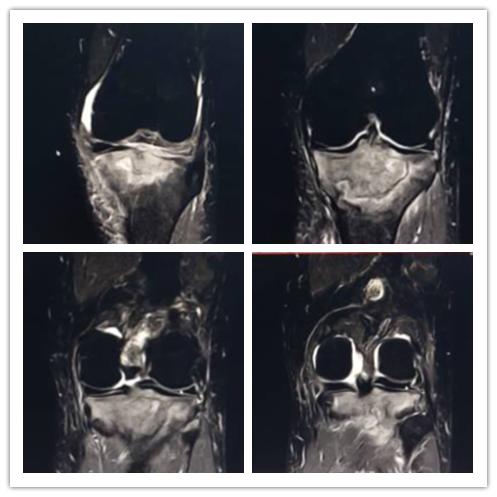

白血病关节病变:周某,男,71岁,既往白血病史,膝关节疼痛一月。

【eT2-TSE COR CLEAR 】

【eT2W-TSE SAG CLEAR】

影像所见:

关节腔及髌上囊见少量积液,左股骨下段及胫腓骨上段见片状异常影,边界尚清,呈地图形,T2WI呈稍低信号影。

【eT2W-SPAIR COR】

【eT2W SPAIR SAG】

【eT1W-TSE SAG CLRAR】

脂肪抑制序列胫骨上端见片状高信号影,信号不均。

【ePDW-TSE COR CLEAR】

内、外侧半月板前后角形态及信号正常,边缘规整,前后交叉韧带、内外侧副韧带及髌韧带形态及信号未见异常。

【T2WI-TSE-CLEAR】